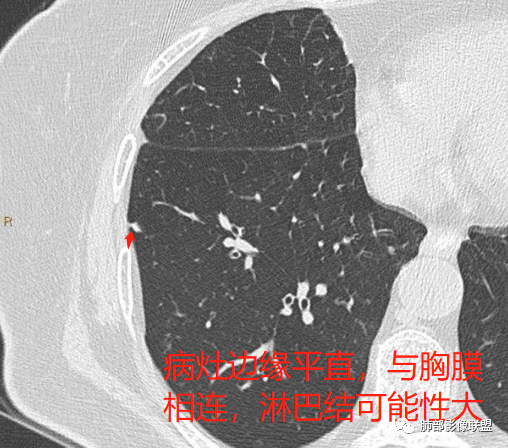

以上病例,有什么共同点?1、病灶均位于胸膜下或叶间胸膜下;

2、病灶边缘多平直,大部分呈三角形,部分呈椭圆形;

3、病灶边缘见一条或数条细线与胸膜相连。

如图所示:

长径均小于12mm。典型的形状为三角形,也可以为梭形、圆形或椭圆形。诊断的关键在于见到1-5条细线与胸膜、叶间胸膜或静脉相连,有时状如坐落于电路板的“二极管”,但以薄层CT显示为佳。有作者病理对照线状影为小叶间隔,有作者病理对照为淋巴管。其实不矛盾,因为淋巴管走行于小叶间隔内。

需要与小肺癌、肺转移瘤进行鉴别。肺内淋巴结除细线状影外,边缘清晰无分叶,无毛刺,没有磨玻璃晕,少张力等是与肺癌鉴别的关键。有作者对9例胸膜下的小于1cm的肺转移瘤进行对照,后者均为较为游离的类圆形,无线状影与胸膜或肺静脉相连。